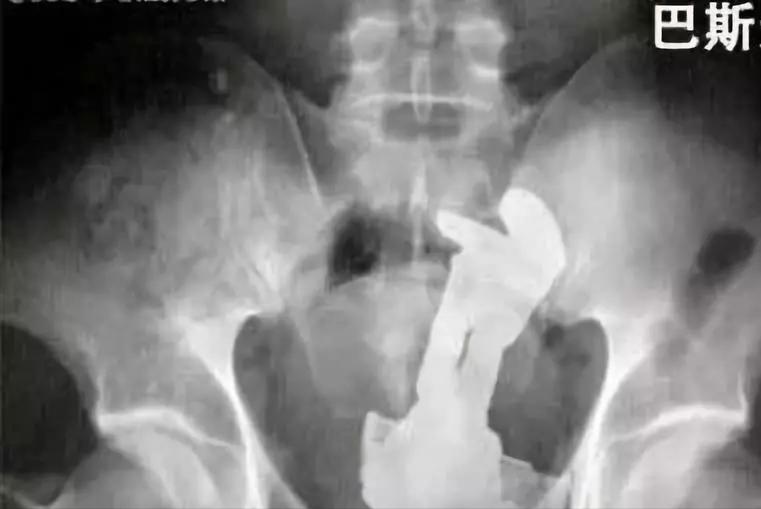

这张图片大家应该并不会陌生,早前曾火爆网络。

说是某地急诊来了位病人,直肠中塞进了“异物”, 但医生万万也不曾想到,异物居然是个灯泡。

只要你活的久,甚至可以在人体内发现巴斯光年。